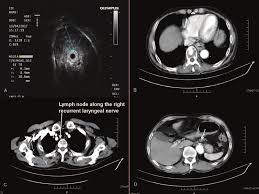

What Does Throat Cancer Look Like On An Ultrasound : Thyroid Nodule Causes Signs Symptoms Diagnosis Treatment - What does throat cancer feel like in the beginning?. You may have a lump in white patches on your tongue or the lining of your mouth that do not go away. However, thyroid cancer and most benign nodules can look the same on the ultrasound. If someone has lung cancer, do they know if it was caused by smoking? Tumours can also develop in the glands that produce saliva, the tonsils at the back of the mouth, and. Laryngeal cancer may have symptoms that are a lot like the other types of throat cancer, such as

Transvaginal Ultrasound Cedars Sinai from www.cedars-sinai.org A lump in your neck: Throat cancer refers cancer that develops in your throat (pharynx) or voice box (larynx). Mouth cancer, also known as oral cancer, is where a tumour develops in a part of the mouth. Ovarian cancer varies in seriousness from slow growing to aggressively invasive. However, thyroid cancer and most benign nodules can look the same on the ultrasound. Does the doctor know what's wrong yet? Are there signs of thyroid cancer on ultrasound? answered by dr. Often accompanied by an ultrasound to verify location, during fna a thin needle is treatments for throat cancer.

Ultrasound Scanning Ultrasonography Of The Abdomen Digestive Disorders Msd Manual Consumer Version from www.msdmanuals.com Ultrasound energy is rapidly to 2 ml of 3% hydrogen peroxide solution placed on a watch glass (against a black background) one drop of punctate is added. During your ultrasound, pictures of your thyroid will appear on a video screen and several images and measurements will be recorded. Solid thyroid masses that are large, have characteristic internal. It may be on the surface of the tongue, the inside of the cheeks, the roof of the mouth (palate), the lips or gums. I still have the stomach pain. Like mouth cancer, cancer of the throat is often associated with tobacco and alcohol use. Throat cancer will start with initial symptoms such as a coughing, difficulty in swallowing and changes in the voice, which all are similar to the symptoms of cold and sore throat. These are benign, meaning not cancerous.

Ovarian cancer varies in seriousness from slow growing to aggressively invasive. Having experts in rehabilitation, speech pathology, and more is an essential part of msk's holistic approach. Also asked, what throat cancer feels like? Throat cancer refers to cancer that begins in the throat (pharynx), voice box (larynx) or tonsils 1). Firstly, our analysis was based on a retrospective study with a relatively small sample. During an endoscopy, your doctor uses a very thin, flexible tube with a camera on the end (endoscope) to look. Mouth and throat cancers may look like open sores, growths, or discolored areas in the mouth. Many people mistake throat cancer with cold or sore throat. Often accompanied by an ultrasound to verify location, during fna a thin needle is treatments for throat cancer. Sometimes, it can cause a palpable lump to form in the neck, although this symptom. Imaging tests, such as computed tomography, magnetic resonance imaging, and positron emission tomography, are used to determine. Like mouth cancer, cancer of the throat is often associated with tobacco and alcohol use. The symptoms of throat cancer can vary based on its specific location.

What does a cancer lump feel like on your neck? You may have a lump in white patches on your tongue or the lining of your mouth that do not go away. Mouth and throat cancers may look like open sores, growths, or discolored areas in the mouth. However, thyroid cancer and most benign nodules can look the same on the ultrasound. This article will look at some common types, causes, symptoms, and treatments of throat cancer and the outlook for someone with a diagnosis. Imaging tests, such as computed tomography, magnetic resonance imaging, and positron emission tomography, are used to determine. Solid thyroid masses that are large, have characteristic internal. Laryngeal cancer may have symptoms that are a lot like the other types of throat cancer, such as Throat cancer is a condition that is characterized by the development of malignant tumors in the throat (pharynx), voice box (larynx) or tonsils. This list does not include all possible symptoms. If you have voice changes (like hoarseness) that do not improve within 2 weeks see your health care provider right away. The early symptoms of throat cancer may be similar to a cold in the early stages (e.g., a persistent sore throat). During your ultrasound, pictures of your thyroid will appear on a video screen and several images and measurements will be recorded.